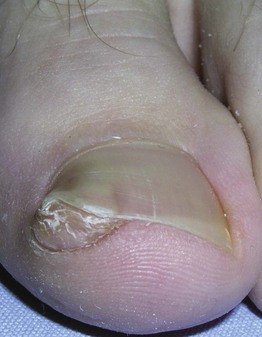

• Painful inflammation of lateral fold with growth of granulation tissue.

• Can be side effect of drugs.

• Rx: see Table 58.1.